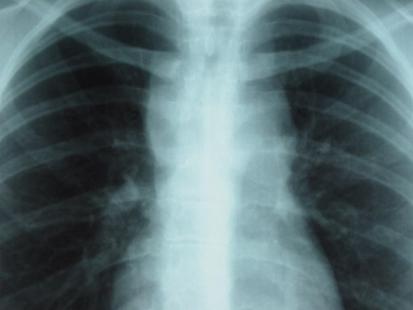

radio

Crédit photo : dr

Dans tous les cas, un prurit qui persiste plus de trois semaines, alors même que la peau apparaît normale, doit conduire à rechercher une cause sous-jacente. Parmi ces causes, et notamment chez un sujet jeune, il faut penser à un lymphome ou à une maladie de Hodgkin. L’examen clinique recherchera des ganglions et la radiographie pulmonaire sera prescrite systématiquement.